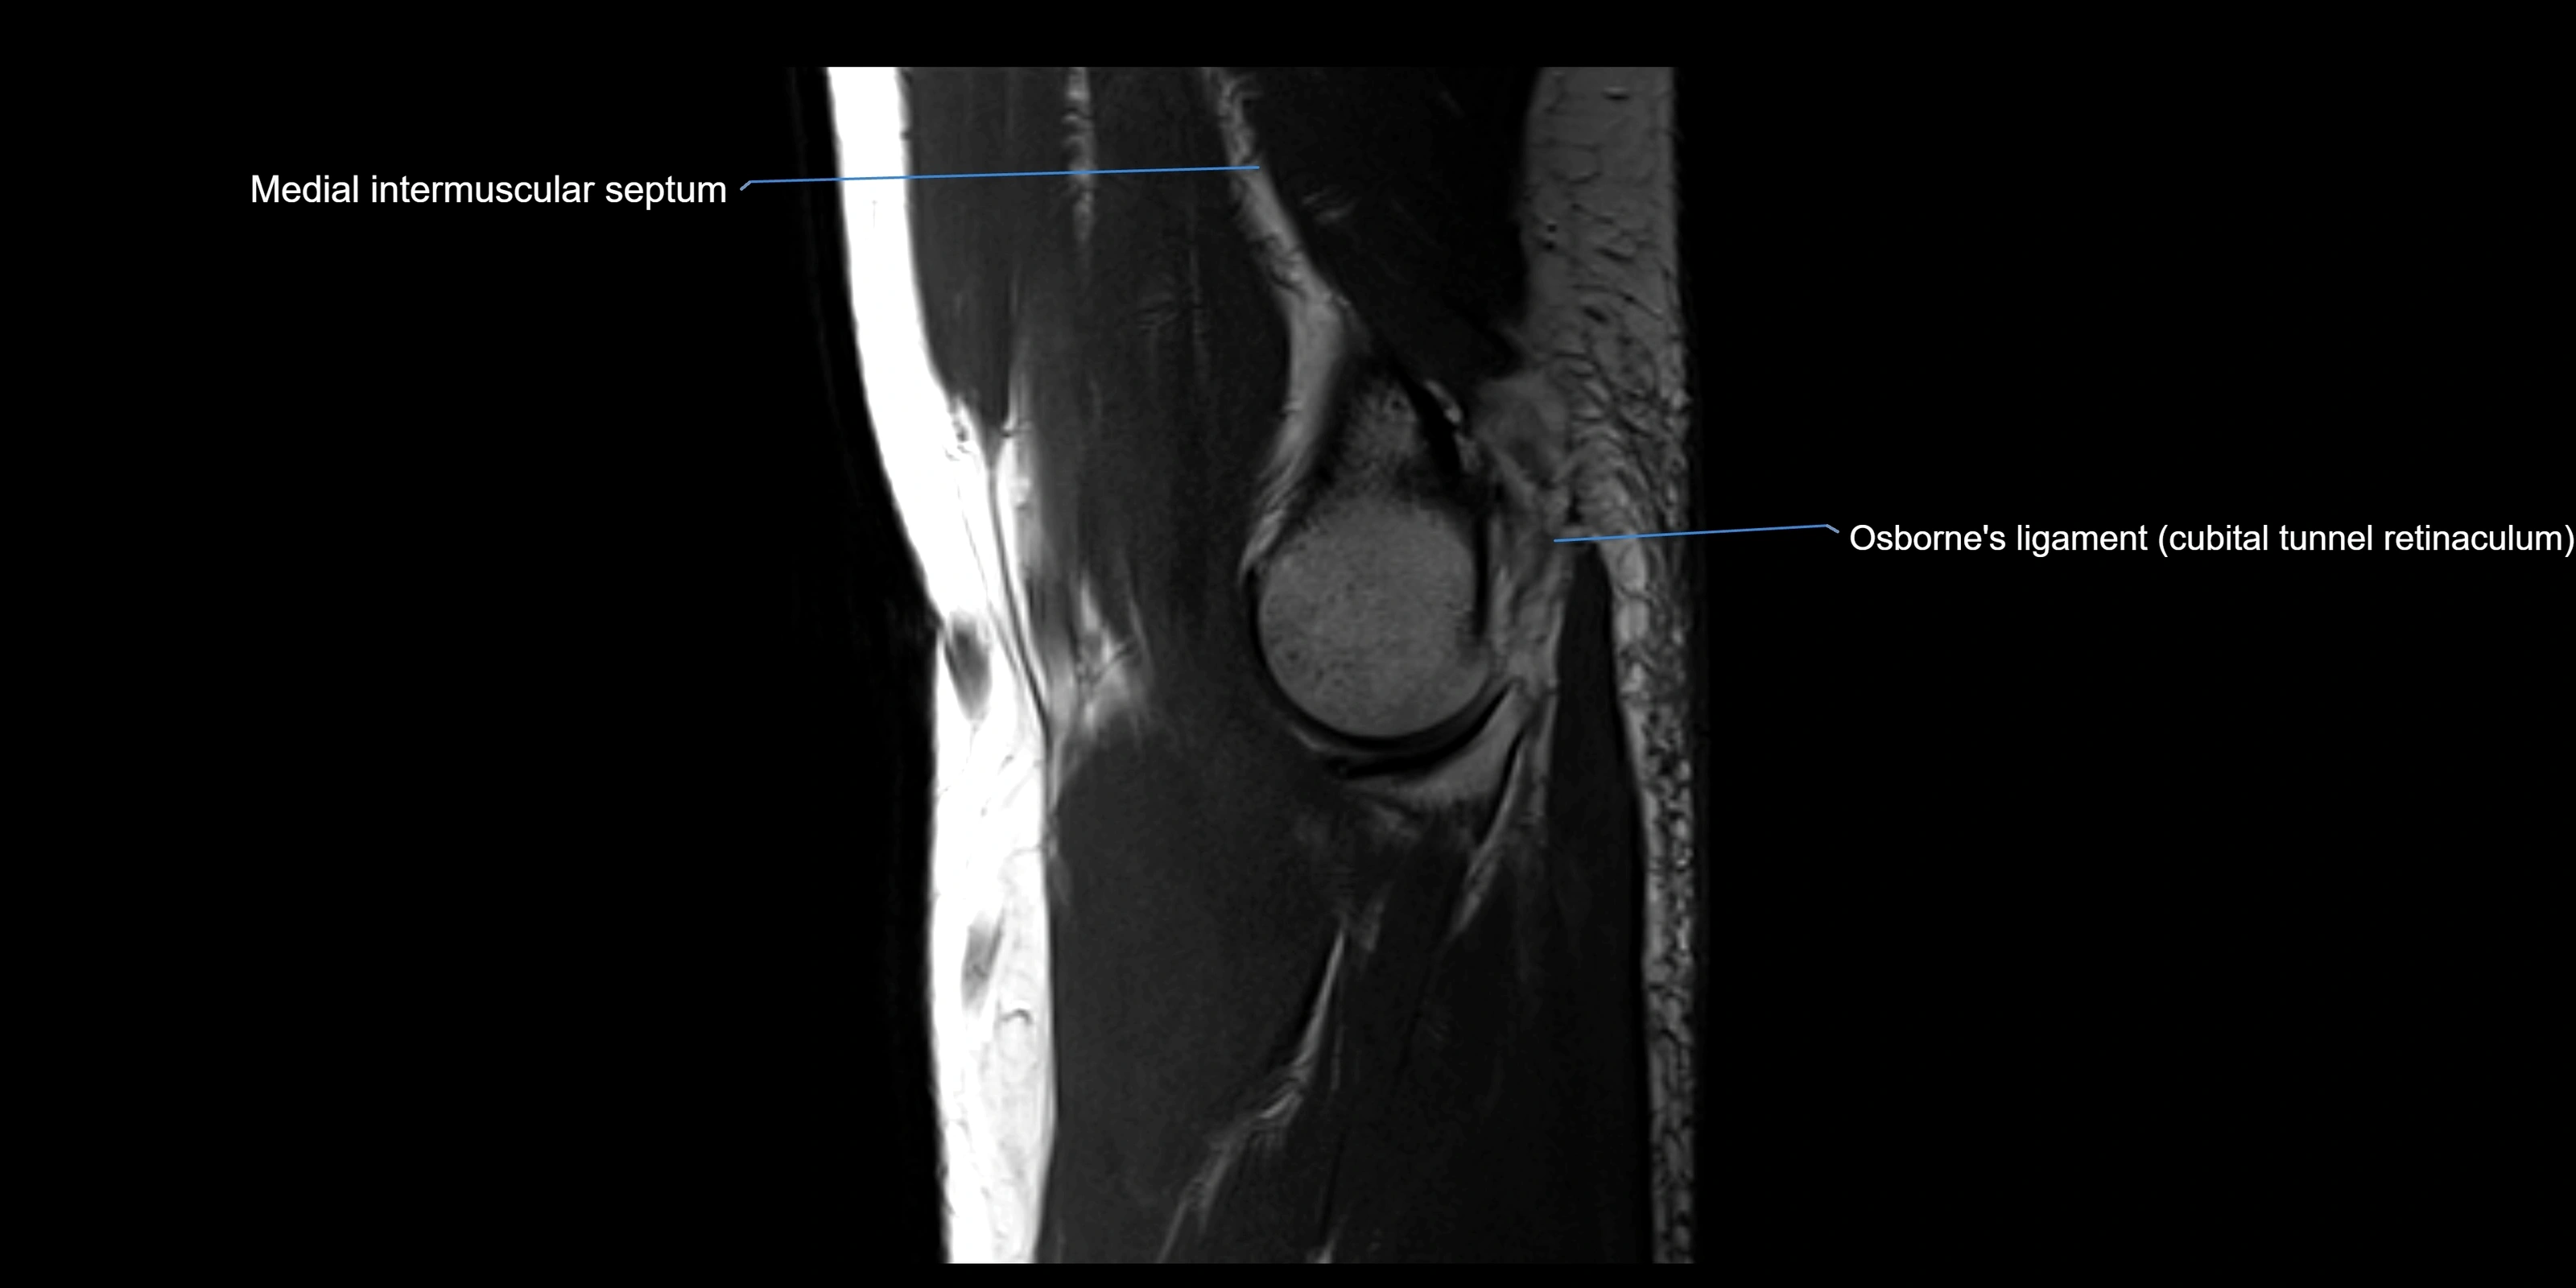

MRI Appearance

T1-weighted images:

• Ligament: low signal intensity (dark), appearing as a continuous band around the radial head.

• Adjacent fat and marrow: bright, creating contrast with the ligament.

• Thickening or disruption indicates injury or fibrosis.

• Joint capsule and synovium seen as thin low-signal lines contiguous with ligament margins.

T2-weighted images:

• Ligament: low signal (dark) with clear delineation from joint fluid.

• Fluid or edema: bright hyperintense, separating or surrounding the ligament in partial tears.

• Complete tear: discontinuity or non-visualization of ligament fibers, often with joint effusion.

STIR:

• Normal ligament: dark band encircling radial head.

• Pathology: bright hyperintense periligamentous signal suggesting edema, sprain, or partial tear.

Proton Density Fat-Saturated (PD FS):

• Normal: dark, well-defined band outlining the radial head.

• Partial tear: irregular or bright hyperintense signal within or adjacent to ligament fibers.

• Joint effusion and reactive synovitis appear bright and are well visualized.